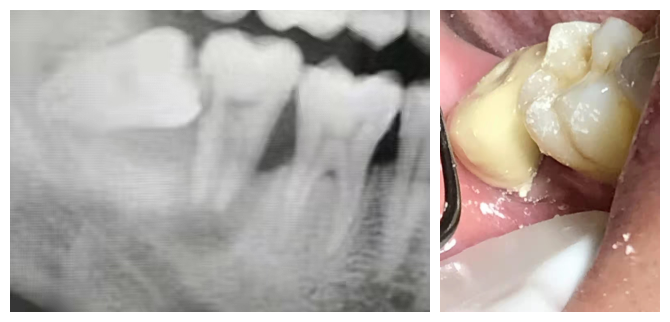

高主任:我對於微創牙科學的理解,在治療過程中儘量減少對牙體或者傷口的損傷之外,能保留的牙齒都儘量保留。去年有一位34的男士,阻生智齒因為沒有及時拔除,導緻7號牙嚴重鬆動,去了其他牙科都建議拔除,後來他經家人介紹到我就職的牙科,經過檢查之後還是儘量幫他保留,拔智齒時,先把這個極松的7號牙和6號牙用玻璃離子粘結穩,先將7牙磨低磨小開髓置Fc棉暫封,然後拔掉智齒,等7牙慢慢恢復。現在7號牙通過冠修復之後成功保留了!